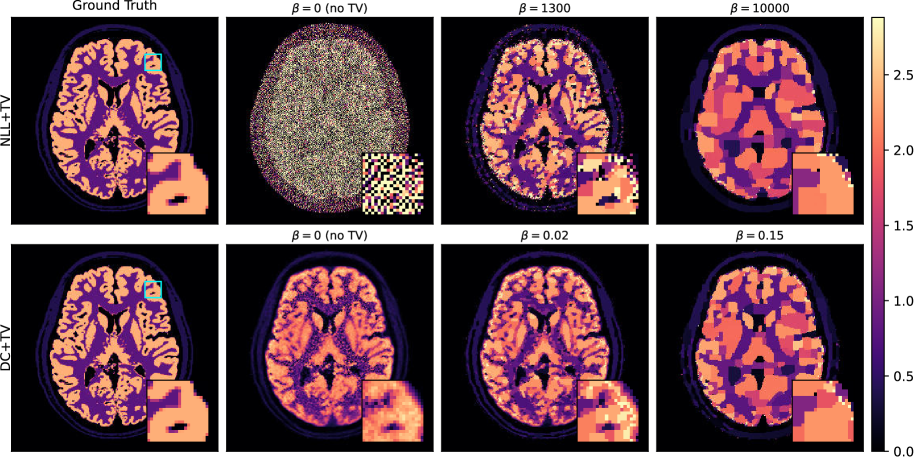

5.2.1 Regularization with DC loss

Regularization is commonly used in medical image reconstruction to compensate for the noise–fitting tendency of standard data-fidelity terms. We therefore augmented the PET image reconstruction objective with a regularization penalty, which introduces the regularization strength hyperparameter β\beta

(𝐱,𝐦)=NLL(𝐱|𝐦)+βTV(𝐱).\ell(\mathbf{x},\mathbf{m})=NLL(\mathbf{x}|\mathbf{m})+\beta\cdot TV(\mathbf{x})\;. (9)

For this experiment, we reconstructed from 4×4\times lower count data while using an edge-preserving variant of total variation (TV) as the regularization term (details in Appendix F.4).

DC+TV achieved better quantitative accuracy and stronger noise suppression at its optimum β\beta than NLL+TV, as shown by Figure 8. Very notably, even with little to no regularization, DC loss still delivers low NRMSE results. In contrast, as shown in Figure 8(b), NLL+TV required substantially greater regularization to counter noise fitting; the reconstruction with lowest NRMSE is noticeably smoother and less detailed than its DC+TV counterpart. Notably, the optimal β\beta for DC+TV also was orders of magnitude smaller than for NLL+TV (Figure 8(a)); this aligns with our hypothesis that DC loss doesn’t place regularization in opposition to data-fidelity (see Figure 2).

By curbing noise fitting at the data-fidelity term, DC loss enables a more favorable trade-off: weaker regularization suffices to suppress noise without sacrificing detail.

Refer to caption

((a)) NRMSE vs. β\beta; DC+TV reaches a lower minimum.

((b)) Optimal-β\beta images; NLL+TV over-smooths, DC+TV preserves detail.

Figure 8: Edge-preserving TV-regularized PET image reconstruction with different data terms. Under NLL, the regularizer must both suppress noise-fitting and impose structure; with DC loss, noise-fitting is already controlled, so the regularizer can concentrate on promoting desirable properties. This yields lower error and better detail at smaller β\beta for DC+TV than for NLL+TV.